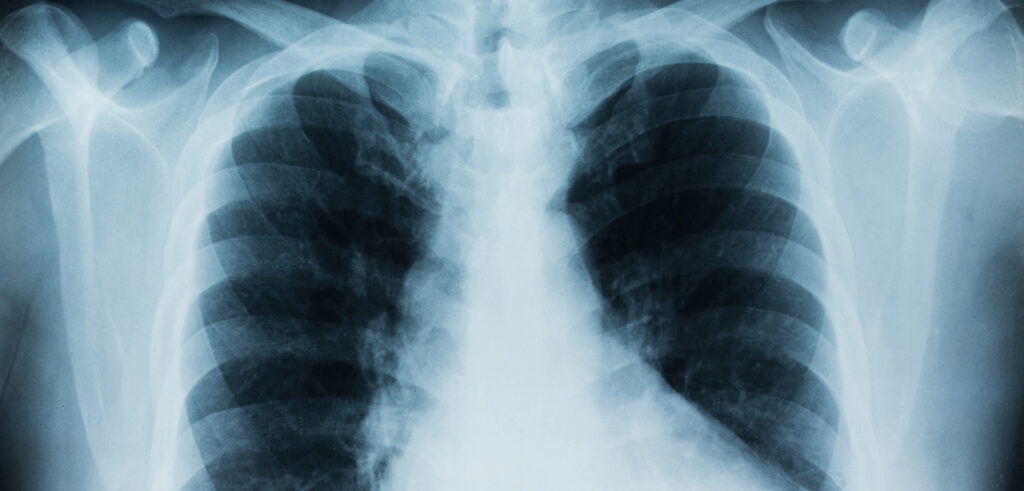

Radoon ja kopsuvähk: uus uuring näitab ootamatult tugevat seost

Värske teadusuuring “Mapping radon levels and lung cancer risk in the UK”, mille viis läbi Queen’s University Belfast Põhja-Iirimaalt, toob esile olulise seose radoonitaseme ja kopsuvähi riski vahel ning annab uusi teadmisi, kuidas seda ohtu paremini hinnata ja ennetada.

Foto: Queen’s University Belfast (artikli juures avaldatud pilt)